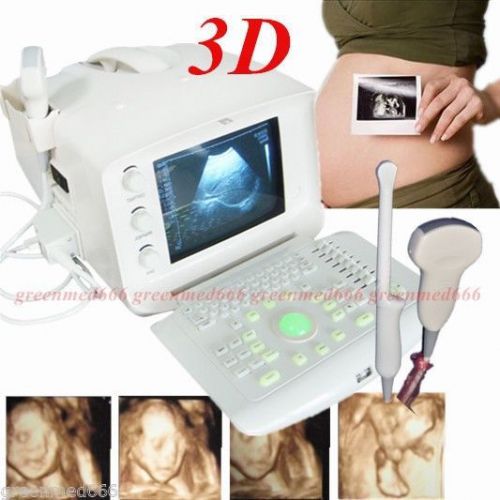

| Model | RUS-9000F |